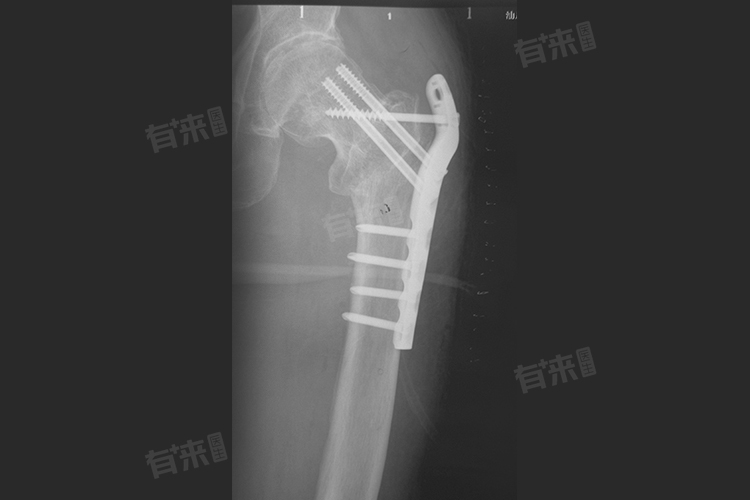

2、钢板数量与规格:当体内仅有一块普通规格的钢板时,取出费用相对较低,大概在2500-4500元,若存在多块钢板,或者钢板尺寸较大、形状特殊,增加了手术取出的难度和时间,费用会相应提高,可能达到4500-7000元。